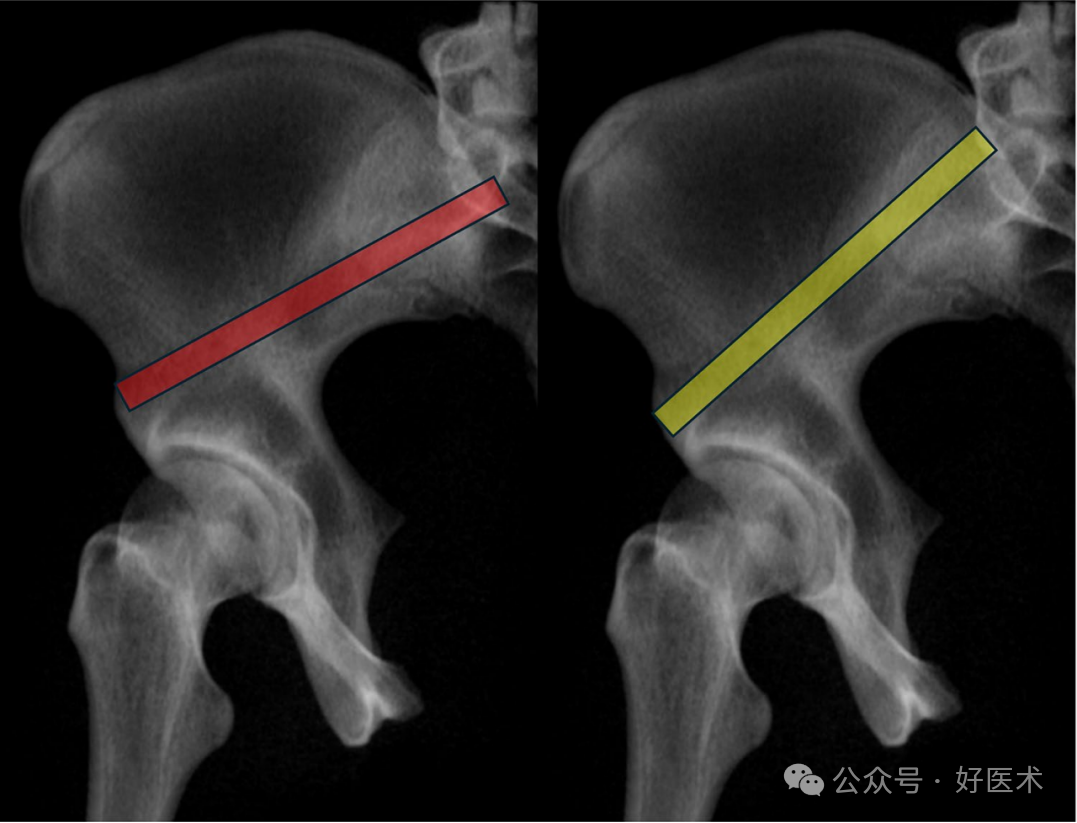

从后部开始到**个狭窄区域的距离,男性约为 3 厘米,女性约为 2.7 厘米。在上方通路(PSIS-AIIS),男性到第二个狭窄区域的距离为86.3mm,女性为84.1mm;在下方通路(PIIS-AIIS),男性为60.3mm,女性为52.8mm。因此,在这个通道中使用长螺钉进行三点稳定是可能的。髋臼上缘通道(SAC)的平均直径在男性中为8.3毫米,在女性中为6.2毫米。这种差异是由于女性的髂骨更呈S形。一种更大的替代髋臼上缘通道在男性中测量为11.3毫米,在女性中为9.9毫米。这种替代髋臼上缘通道的起始点更靠下(位于髂前下棘AIIS的下方),出口点位于骶骨后上棘(PSIS)的前方,导致其角度更偏向头侧(图19)。这种替代髋臼上缘通道(SAC)存在进入关节内的风险,因为髋关节囊附着点可延伸至髋臼缘上方1.6厘米处。

图19 替代髋臼上缘通道(SAC)与标准通道相比,起始点更靠下(位于髂前下棘AIIS的下方),且角度更偏向头侧(黄色为替代通道,红色为标准通道)。